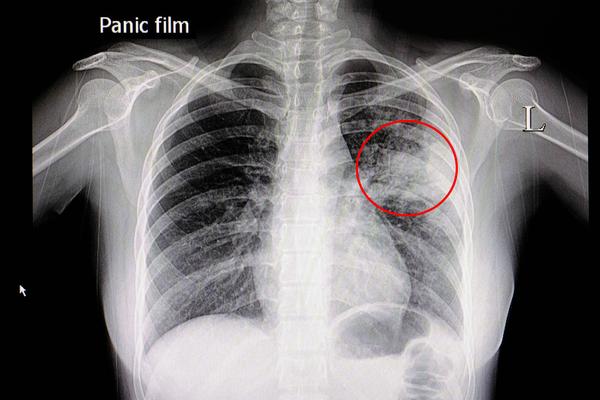

肺气肿的影像诊断

求助喘憋无胸痛症状胸片是立位

肺功能检查正常,但胸片说可能是肺气肿,请医生看一下胸片是不是肺气肿

肺气肿胸片影像

肺气肿的胸片表现